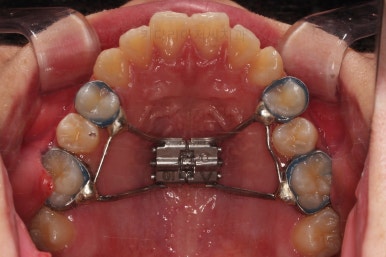

동래교정치과 초진 시 입안의 모습입니다.

치아가 벌어진 것도 벌어진 것이지만 교합이 전혀 안되고 있었어요.

틈새도 아랫니에 훨씬 많았고요.

윗니가 있는 위턱뼈가 전반적으로 아래턱에 비해 3차원으로 작은 양상이었습니다.

이번 환자분은 아랫니가 전반적으로 앞이든, 뒤든, 양옆으로든 넓어져 있는 양상이었고 그래서 아랫니에 틈도 많고 아래 앞니도 밀려나와 있는 양상인거죠.

동래교정치과 첫 단계로 악궁확장 장치를 했습니다.

이미 틈새가 있는데 악궁확장이라고요?

보통 공간이 부족할 때 공간 마련 목적으로 악궁확장을 한다고 오해하고 계신 분들이 상당히 많은데요.

악궁확장을 하면 공간이 더 확보된다는 것은 분명한 사실이지만 공간마련을 위해서 악궁확장을 하는 것이 아닙니다.

위턱과 아래턱의 폭이 맞지 않을 때 위턱을 넓혀주는 것이 악궁확장인데요.

그러면 어쩔 수 없이 틈새가 있어도 넓은 아래턱과 조화가 맞게 위턱을 더 넓힐 수 밖에 없습니다.

그래야 교합이 맞아지니깐요.

다시 한 번 말씀드리지만 악궁확장의 목적은 위턱과 아래턱의 폭의 조화입니다.

공간이 더 생기는 것은 장점이 될 수도 단점이 될 수도 있는 부수적인 현상일 뿐이고요.